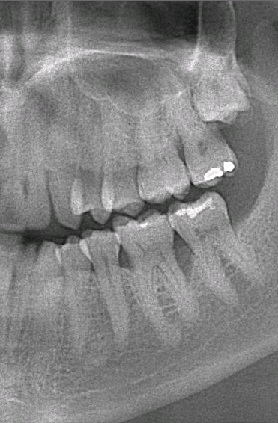

Perioscopy results

Another lovely result of non-surgical gum treatment using Perioscopy. Lucky for this tooth, there is now more bone to support it in the gum. Keeping your back teeth are in good periodontal shape will not only help with chewing your food but will also preserve the health of your front teeth.